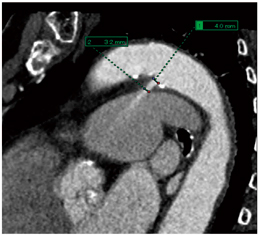

volume rendering(VR)の4Dでは,造影剤が左心室から大動脈に流れていく状態と,PDAの位置を任意の角度から確認することができる(図3)。また,multiplanar reconstruction(MPR)の4Dでは,VRでは確認できない任意の断面の状態や,肺動脈へのジェットの状態を確認することができる(図4)。また,MPRでは,PDAの径を計測することも可能である(図5)。

![]() 図5 PDA症例のMPR計測 |